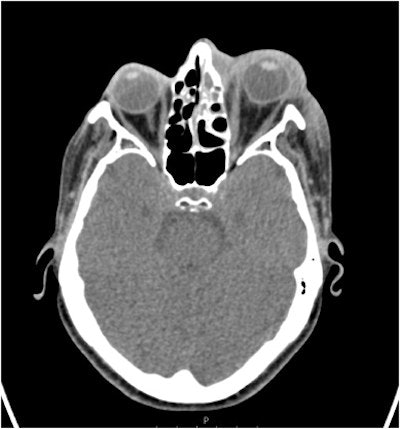

Computed tomography (CT) scans revealed swelling and fluid around the woman's eye and partial opacification of her maxillary sinus and aided in the diagnosis of the rare but deadly bacterial infection, odontogenic orbital cellulitis. Surgery treated her infection but the woman has complete vision loss in her left eye, they wrote.

CT scans showed that her sinuses had significant preseptal and postseptal swelling with retro-orbital fat stranding with small volume fluid noted at lateral and superior left orbit, with no drainable collection in the orbit. The imaging also showed partial opacification of the patient's left maxillary sinus and anterior ethmoid air cells. The scans showed that her condition met the criteria for orbital cellulitis, they wrote.